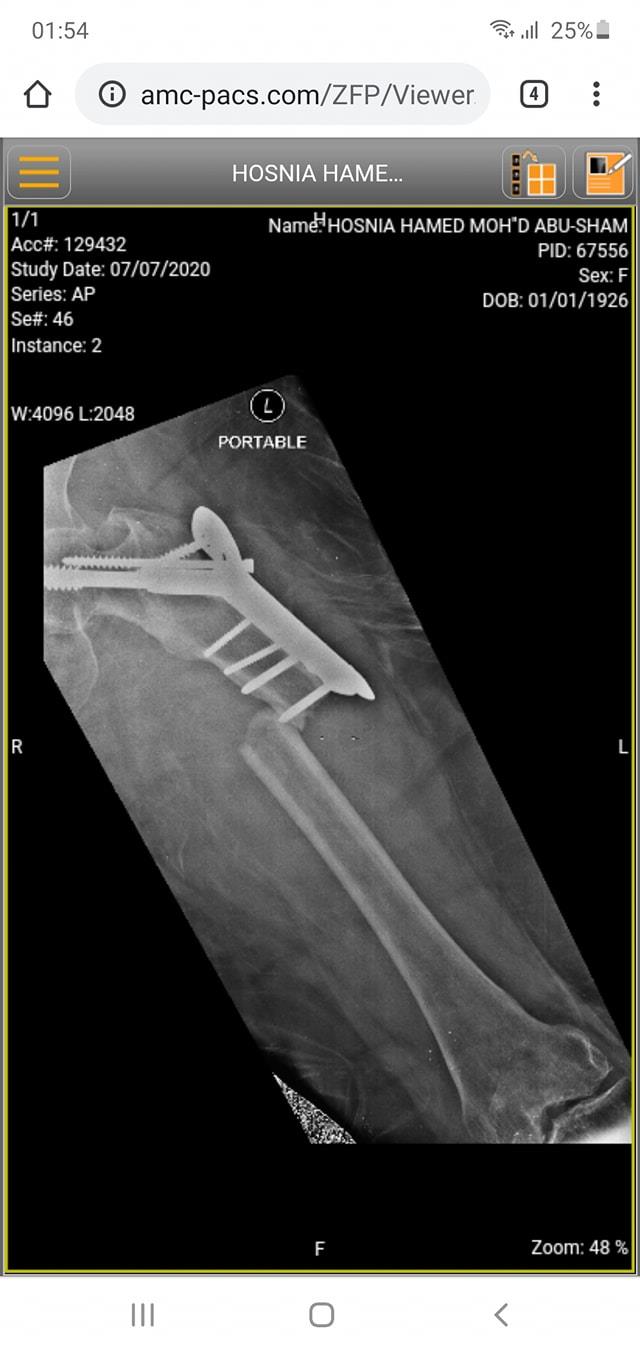

كافة انواع الكسور وعلاجها